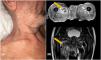

Reportamos el caso de dos pacientes con eritrodermia y absceso en la cadera. La paciente 1 es una mujer de 70 años que presentó eritrodermia psoriásica persistente a pesar del tratamiento con etretinato, metotrexato y ciclosporina (fig. 1A). Fue ingresada en el hospital en marzo de 2021 con PASI (Psoriasis Area and Severity Index) de 41 y ASC (área de superficie corporal) de 58. Las placas psoriásicas eran inflamatorias, con pústulas en la superficie, pero sin claras erosiones. Transcurrido un mes, reportó dolor en el muslo izquierdo. No se detectaron anomalías en una radiografía de la cadera ni tampoco en una ecografía de partes blandas. En el plazo de una semana desarrolló escalofríos y fiebre. La analítica fue positiva para SA sensible a meticilina (SASM). Sospechándose una complicación infecciosa en la cadera se solicitó resonancia magnética (RM), que reveló un absceso a nivel del músculo iliaco.

El paciente 2 es un varón de 76 años con historia de brotes eccematosos en los dos años previos. Fue ingresado en el hospital por brote de eritrodermia con linfadenopatías (fig. 1B). La biopsia cutánea confirmó la sospecha clínica de micosis fungoide. Las pruebas complementarias no mostraron clonalidad en sangre periférica ni en ganglios, por lo que se estableció diagnóstico de micosis fungoide en estadio IIIa (T4N1aM0B0). Durante los días siguientes, el paciente desarrolló malestar, fiebre y dolor de cadera. Los cultivos de sangre fueron positivos para SASM y Streptococcus pyogenes. Un TC de cuerpo entero mostró un absceso iliaco. Se descartó endocarditis, ya que el paciente portaba una válvula cardiaca mecánica (fig. 2).